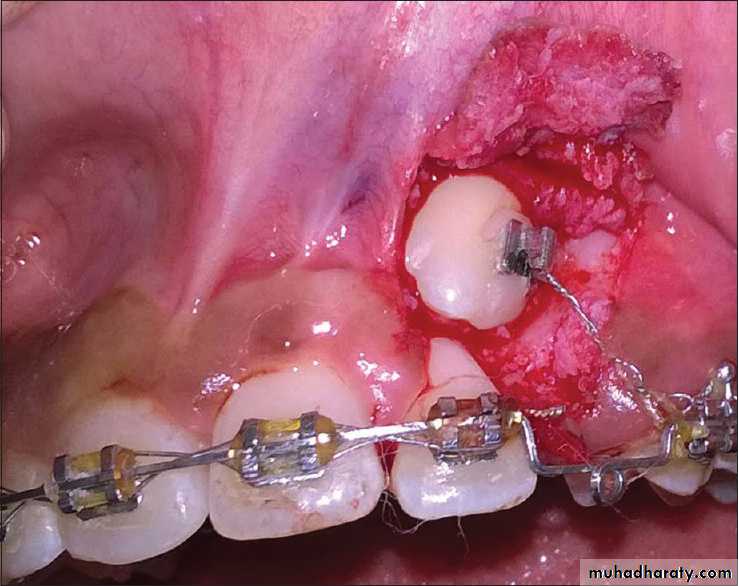

More rarely a buccally displaced canine tooth does not erupt or its eruption is so delayed that treatment for other aspects of the malocclusion is compromised. In these situations exposure of the impacted tooth may be indicated. To ensure an adequate width of attached gingiva either an apically repositioned or, preferably, a replaced flap should be used. In the latter case, in order to be able to apply traction to align the canine, an attachment can be bonded to the tooth at the time of surgery. A gold chain or a stainless steel ligature can be attached to the bond or band and used to apply traction.

• (4) Commence traction. Traction can be applied using either a removable appliance ( Fig. 14.10 ) or a fixed appliance ( Fig. 14.11 ). To complete alignment a fixed appliance is necessary, as movement of the root apex buccally is required to complete positioning of the canine into a functional relationship with the lower arch.